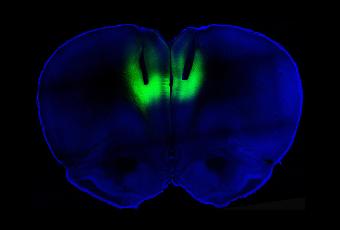

Para saber si esas neuronas inactivas a su vez generaban el comportamiento compulsivo, los científicos recurrieron a una técnica llamada optogenética, que utiliza la luz para activar neuronas dentro o fuera. Los investigadores inyectaron a las ratas virus que insertan moléculas sensibles a la luz en las neuronas perezosas. Cuando los investigadores usaron rayos láser para estimular las neuronas en las ratas compulsivas, están empujaron las palancas a un tercio de la frecuencia. El mismo experimento en usuarios no compulsivos no tuvo ningún efecto.

Los investigadores invirtieron después el experimento, usando láseres de nuevo, pero esta vez, para apagar las neuronas de los sujetos no compulsivos. Esas ratas empezaron a empujar las palancas de cocaína casi con tanta frecuencia como las otras ratas.